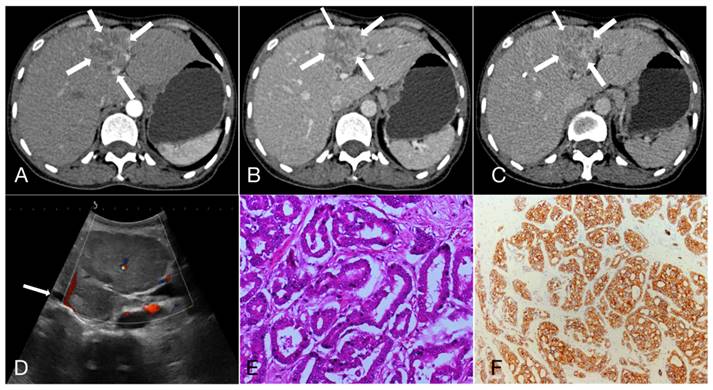

Figure 1

A 55-year-old female patient with hepatocellular carcinoma (3.7cm×3.3cm), accompanied by liver cirrhosis and splenomegaly. A, B, C. In multiphase enhanced computed tomography, the nodules exhibit overall hyperenhancement during the arterial phase, with indistinct regression during the portal and equilibrium phases, showing Iso- or hyper enhancement. D. Ultrasound demonstrated a mixed echo nodule in the segment 4 of the liver with Grade-I of blood flow; E. Hematoxylin and eosin staining, ×200; F. The immunohistochemical marker Hepatocyte, ×100.

As shown in Table 3, 47.3%, 22.3% and 30.4% of HCC showed APHE, partial APHE, and rim APHE in the arterial phase, while the percentages of ICC with these imaging features were 30.6%, 37.1%, and 32.3%, respectively (X2 = 13.374, P=0.001). Hypo-enhancement, delayed enhancement and iso- or hyper-enhancement in the portal and equilibrium phases of CT were observed in 37.6%, 19.5% and 42.9% of HCC, and 58.1%, 25.0% and 16.9% of ICC, respectively. Statistical significance of image features in the portal and equilibrium phases was observed between the two groups (X2=11.222, P=0.001). In brief, peripheral rim-like APHE was more commonly observed in ICC, while early washout in the portal venous phase and equilibrium phase was also more prominent (Figure 1, 2).